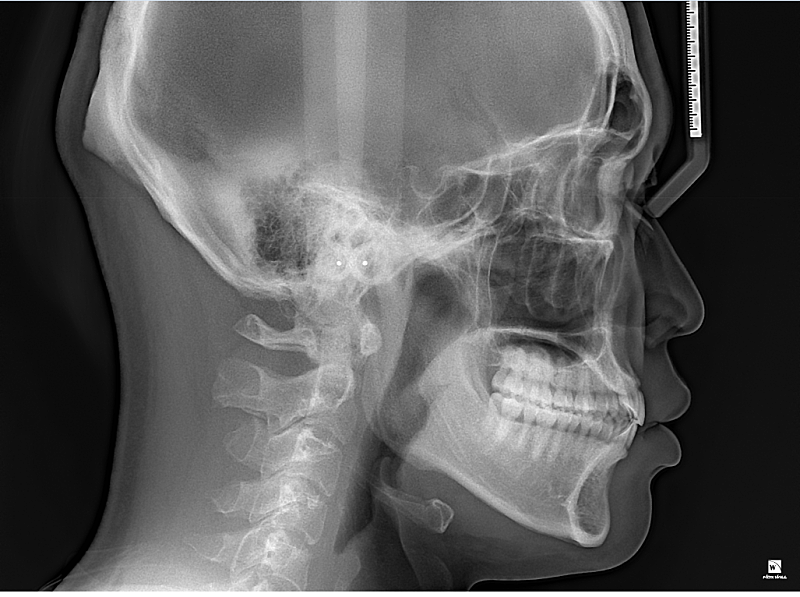

앞니치아가 앞뒤로 1~3mm공간이 없으면 절단교합일까요?

앞니들 전후방적으로 1~3mm 정도 공간을 두는게 정상치아 교합일까요?

저는 앞뒤로 공간이 없어보이는데 치아가 마모될수도 있을까요 제앞니 어떼보이시나요?

치아끼리 부딪히면 절단교합이라 봐야하나요??

절단 교합은 상 하악 앞니가 정확히 일직선으로 맞물려야 합니다. 따라서 지금 정도로 절단교합이라고 하지 않습니다. 또한 음식 섭취 시 앞니는 음식을 간단히 끊는 용도이지 실제로는 어금니가 모든 역할을 합니다. 따라서 해당 치아가 현재로 맞물린다고 해서 마모되지 않습니다. 지금 정도는 교정 중이기 때문에 잘못되었다고 볼수도 없고 절단교합 및 이상이라고 하지 않습니다. 치료를 충실히 받으시길 바랍니다.

절단교합은 위아래 치아의 끝부분끼리 정확하게 맞닿는 상태를 의미합니다.

사진으로는 오른쪽은 절단교합이 아닌 정상교합이며, 왼쪽은 측절치가 애매하게 보이긴 합니다.

말그대로 절단교합은 앞니 끝과 아래니의 끝이 교합이 되는 상태를 말합니다. 사진상으로 보면 절단교합은 아니신거 같아요.